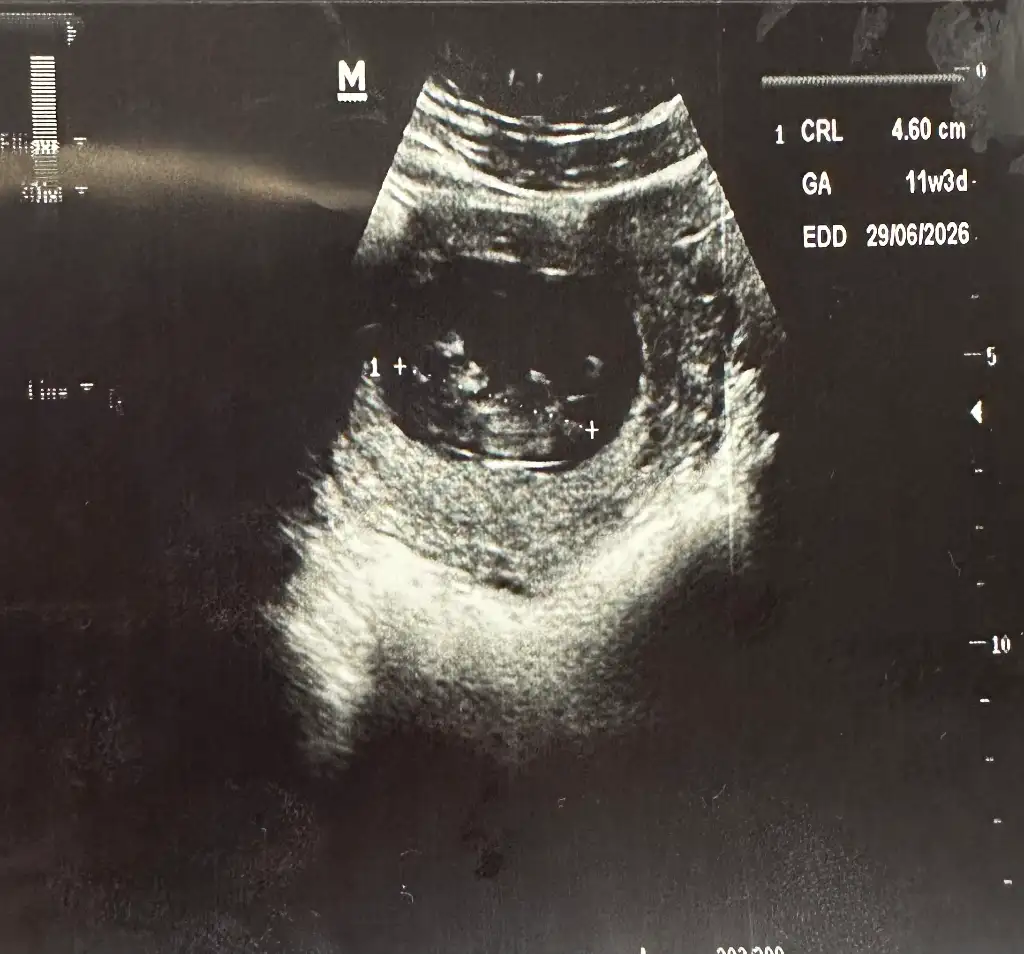

Maşallah yaaa yine de net görünüyorBen bugün muayeneye gittim kızlar, doktor multivitamin ve demir başlayalım dedi. Bebiş de 4.6cm olmuş içerde narin narin kayıyorducihaz çok kötüymüş devlet hastanesiydi ama baksanıza

Ya sen geçen hafta da muayenede değil miydinBen bugün muayeneye gittim kızlar, doktor multivitamin ve demir başlayalım dedi. Bebiş de 4.6cm olmuş içerde narin narin kayıyorducihaz çok kötüymüş devlet hastanesiydi ama baksanıza